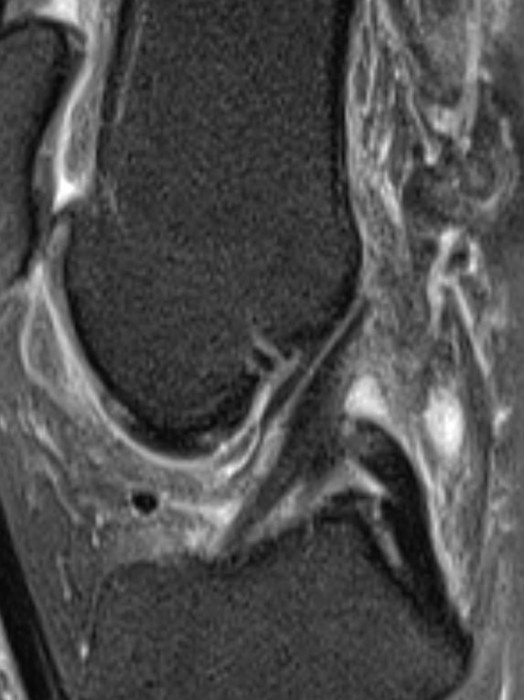

Patient de 44 ans presentant une masse peu sensible de la face palmaire du poignet avec des.

Une anomalie des membres caracterisee par labsence congenitale dun membre a partir du coude. Tumeurs pseudo tumeurs thrombose veineuse ulnaire du poignet irm.